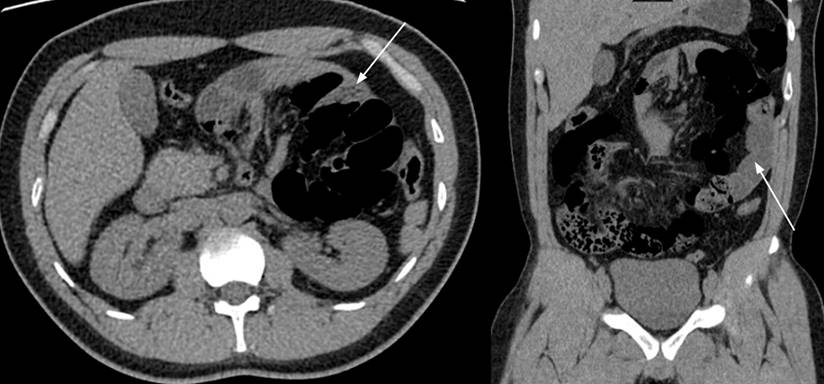

Se trata de un paciente masculino de 29 años, sin antecedentes médicos ni quirúrgicos. Ingresó al servicio de urgencias por un cuadro clínico de 24 horas de evolución consistente en dolor abdominal de inicio súbito, tipo cólico, localizado en el mesogastrio y el flanco izquierdo, acompañado de distensión abdominal y emesis, irradiado a la región paravertebral izquierda y a la fosa ilíaca izquierda. En el examen físico se documentó taquicardia sinusal, abdomen distendido y dolor a la palpación profunda acentuada en el hemiabdomen izquierdo, sin signos de irritación peritoneal. Los paraclínicos evidenciaron leucocitosis (15 000 cél/μL), neutrofilia (12 750 cél/μL), proteína C-reactiva elevada (16 mg/dL). Inicialmente, se sospechó una urolitiasis con efecto obstructivo, por lo que se realizó una urografía por tomografía (uroTAC) simple, que evidenció un conglomerado de asas intestinales ubicadas hacia el hemiabdomen izquierdo con edema intestinal difuso y escaso líquido entre las asas (Figura 1).

Figura 1 UroTAC en la que se observa un corte axial y coronal, respectivamente. Las flechas señalan el conglomerado de asas intestinales en el hemiabdomen izquierdo. Fuente: archivo de los autores.